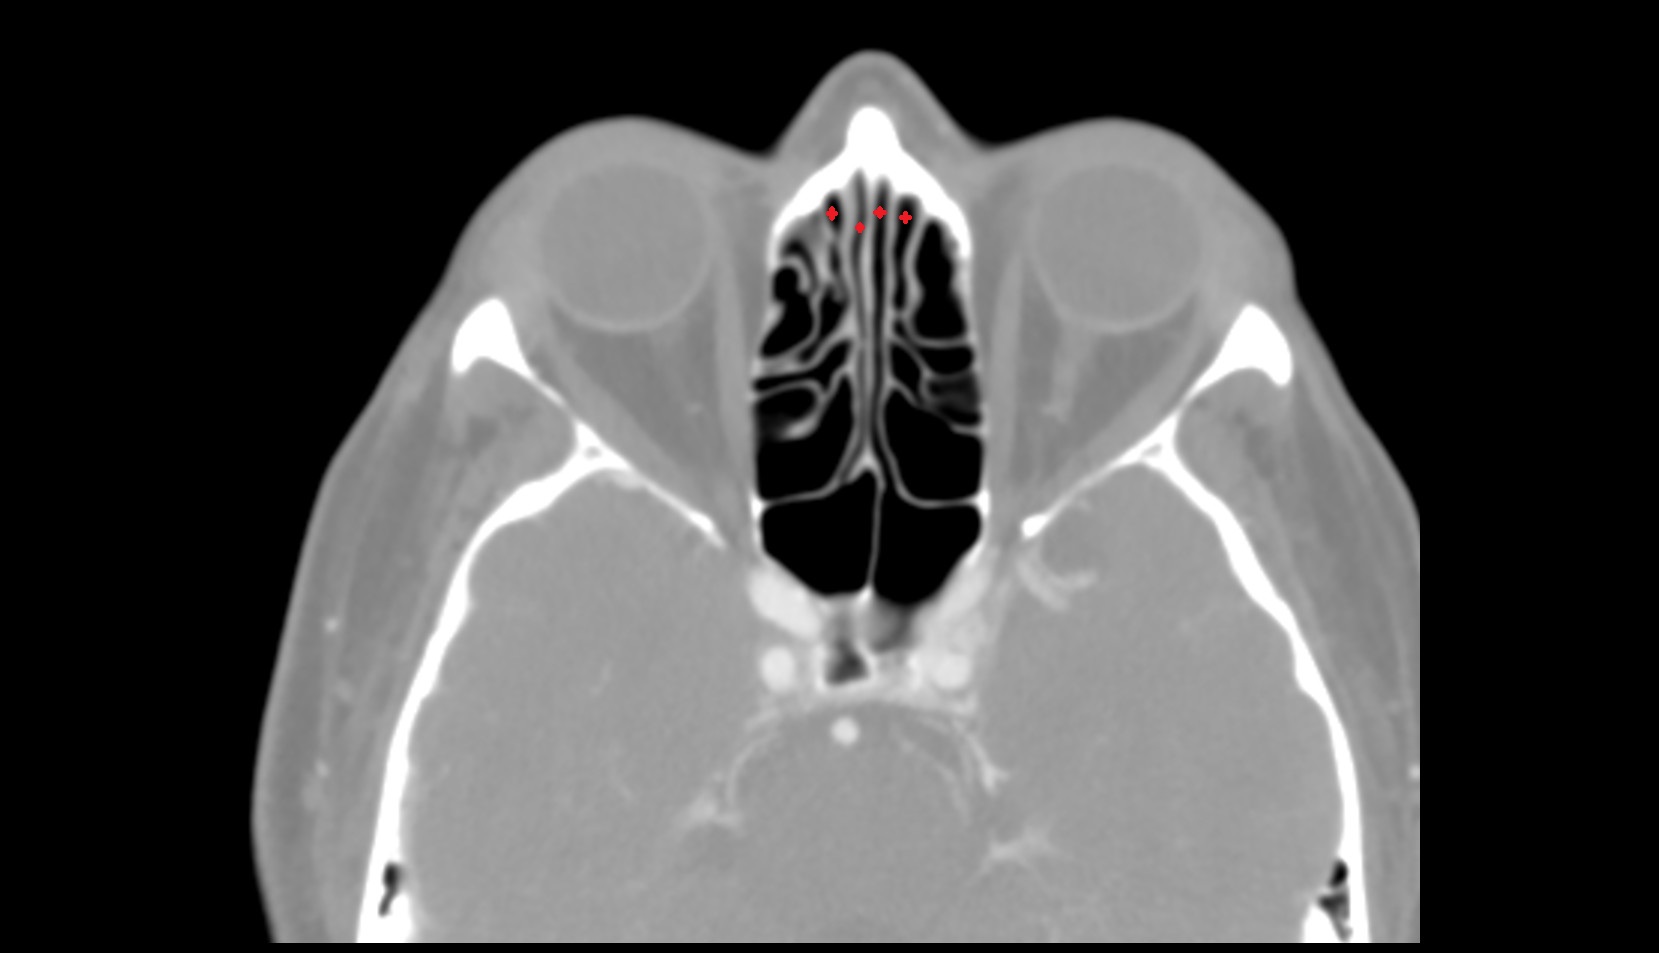

- Clivus

- Inferior nasal concha

- Middle nasal concha

- Nasal septum

- Superior nasal concha

- Vomer